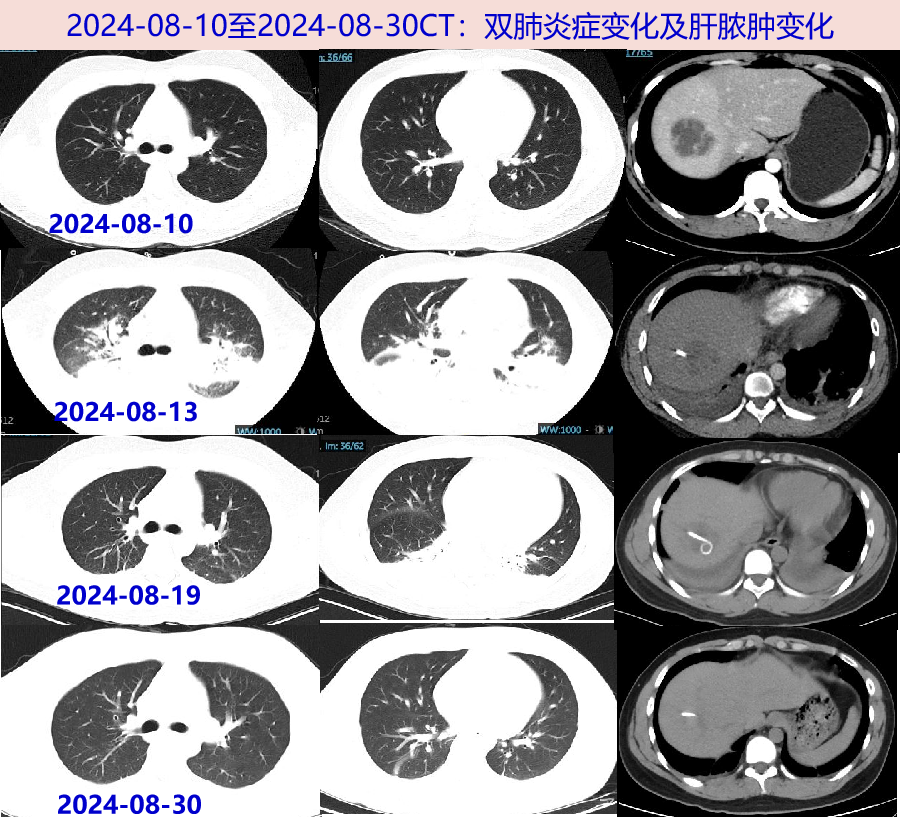

• 2024-08-05 无诱因下出现发热,Tmax 40℃,伴畏寒寒战、头晕头痛,呕吐胃内容物1次。08-09就诊我院门诊,查WBC 18.9×109/L,N 81.9%;CRP 185mg/L;新冠、甲乙流、呼吸道合胞病毒、腺病毒、鼻病毒、肺炎支原体核酸均阴性。胸部CT平扫:未见活动性病变,附见肝右叶低密度灶。颅脑CT平扫未见异常。予左氧氟沙星0.5g抗感染,寒战高热无好转。

• 2024-08-10 仍有寒战高热,Tmax 40.5℃。至我院门诊复诊,查WBC 15.2×109/L,N 81.9%;CRP 238.5mg/L,PCT 0.74ng/L;TB/DB 28.9/10.5μmol/L,ALT/AST 36/34U/L;D-二聚体 0.35mg/L。腹盆增强CT:肝脓肿,脂肪肝。肝脏B超: 肝右叶混合性占位,大小43*38mm—考虑脓肿形成可能。建议住院,患者拒绝。当日至急诊,考虑细菌性肝脓肿,予厄他培南 1g qd抗感染;介入B超下行经皮肝脓肿穿刺引流术,术中引流出脓血性液体(具体量不详)。08-10夜间出现剧烈呕吐1次,为胃内容物。

• 肺动脉CTA(08-13 ):两下肺动脉分支远端充盈欠均;两肺炎症,两侧少量胸腔积液伴两肺部分不张。

病史特点:青年男性,既往无慢性疾病基础,急性病程,发热伴恶心呕吐、头晕头痛1周余,WBC、CRP、PCT明显升高,入院前8月9日胸部CT及8月10日腹部CT:未见活动性病灶,腹部增强CT见肝脓肿,介入超声下肝脓肿穿刺引流出血性脓液,肝脓肿临床诊断明确,需进一步明确病原学诊断,继续抗感染治疗。追问病史,08-10夜间出现的呕吐较剧烈,为胃内容物,量较多,约500ml,伴呛咳,考虑呕吐后有误吸,出现明显低氧血症,8月13日肺动脉CTA发现,两下肺动脉分支远端充盈欠均、两肺炎症、两侧少量胸腔积液伴两肺部分不张,肺部病变的原因,考虑如下:

• 2024-08-19 胸腹CT平扫:两下肺为著炎症及不张,较24-08-13片部分吸收,两侧少量胸水较前略吸收;肝脓肿穿刺引流术后改变。

• 2024-08-30 肝脏彩超:病灶缩小至21×20mm,较前明显吸收。胸部CT:双侧胸腔积液及两肺炎性病灶基本吸收。继续予莫西沙星片 0.4g qd口服抗感染、利伐沙班片15mg bid抗凝。告知患者可予肝脓肿引流管拔管。